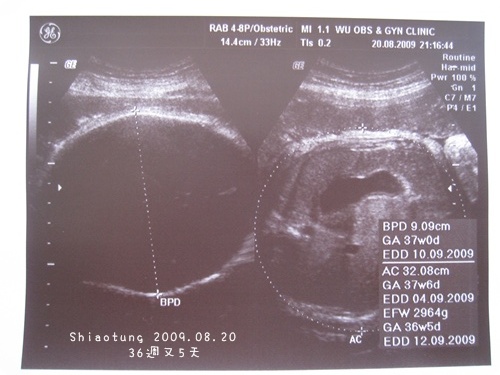

懷孕週數:36+5

胎兒體重:約29xx~30xxg

看看寶寶大小→每星期約多兩百公克左右